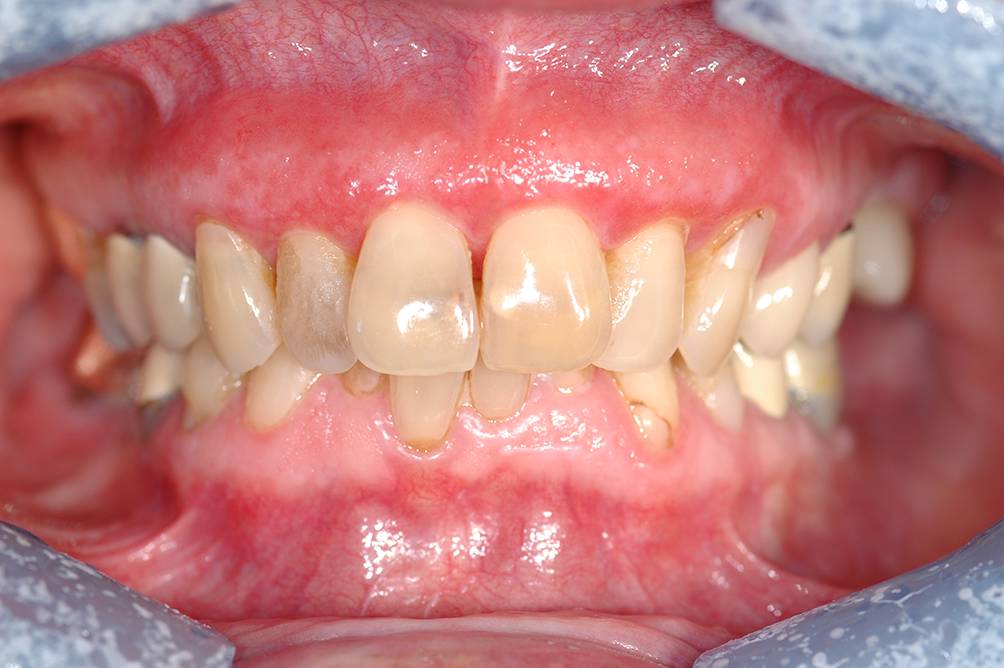

Abb. 5

Typischer plaqueartiger Lichen-Typ mit Befall der Zunge in unterschiedlicher Ausprägung bei einer 73-jährigen Patientin (a) und einem 67-jährigen Patienten (b). Die Zungenoberfläche wirkt weißlich atrophisch, gegen die Zungenränder sind teils auch dezente weißlich-retikuläre Effloreszenzen zu erkennen

Bild vergrößern